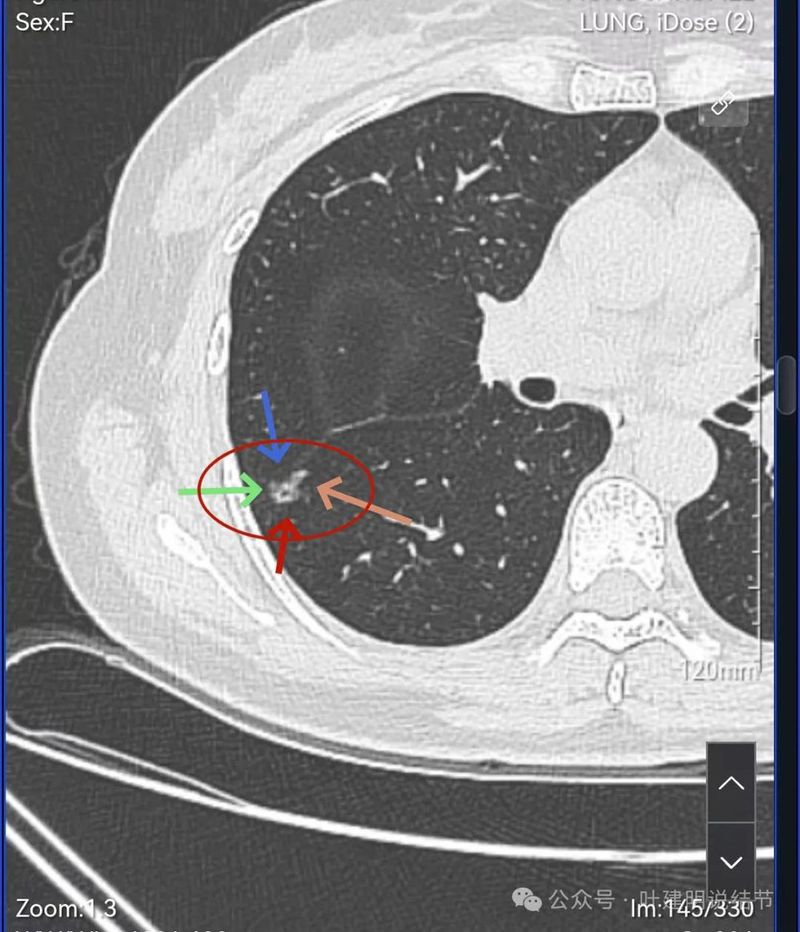

表面分叶,中间空泡,边缘有磨玻璃成分,叶间胸膜凹陷。

灶内血管穿行,表面分叶、中间空泡,实性成分。

血管进入,表面分叶,密度不均。

密度显杂乱,血管贴边。

右肺多发磨玻璃结节,红色的是主病灶,密度不纯,贴着叶间裂,分叶明显,考虑至少微浸润性腺癌,也可能是浸润性腺癌贴壁为主型,不能继续随访,建议手术切除,可以单孔胸腔镜下局部楔形切除。黄色的也是磨玻璃,不典型增生或者肺泡上皮增生可能性大,蓝色的肺泡上皮增生可能性大。这两处风险还低,但如果主病灶需要处理,也可以考虑同期切除。意见供参考!